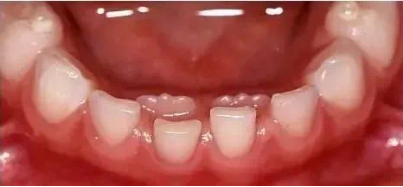

八字队形

小朋友刚萌出的乳门牙或恒门牙呈“八字”形,需要干预吗?

图片

对于乳门牙的“八”字形排列,如果上下牙齿之间的咬合是正常的,一般不需要干预,这个阶段注意关注孩子是否有一些不良的口腔习惯(如吃手、啃指甲、躺着喝奶等),如果有可予以纠正,并定期复查即可;乳牙八字形并不代表恒牙也一定会八字形排列;

如果换牙后仍然呈“八字”排列,建议7岁左右进行正畸评估,一般来说单纯的“八字”排列不需要立即干预,可以等牙齿换完后再进行调整;如果合并牙弓狭窄、咬合干扰等问题则可能需要早期干预